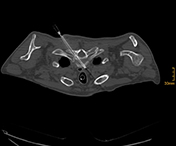

Nach Innsbruck kam Glodny aufgrund eines persönlichen Treffens mit o. Univ.-Prof. Dr. Werner Jaschke, dem Leiter der Innsbrucker Universitätsklinik für Radiologie. „Aus einem zunächst nur kurz angesetztem Termin bei ihm wurde ein mehrstündiges Gespräch, in dem ich erfahren habe, was hier in Innsbruck alles möglich ist und wie ich hier arbeiten kann“, erzählt Glodny rückblickend. Insbesondere die interventionelle Radiologie, durch die vielfältige therapeutische Eingriffe etwa in der Behandlung der arteriellen Verschlusskrankheit, oder von Blutungen oder Aneurysmen, von Tumoren- oder Metastasen möglich geworden sind, fasziniert den Radiologen und Forscher. „Mit durch Hochfrequenzstrom erzeugter Hitze, z. B. dem Verfahren der sogenannten Radiofrequenzablation, können Tumore oder Metastasen in Organen wie Leber, Niere oder Lunge behandelt werden. Die Vorteile dabei sind, dass ein oder mehrere Tumore extrem zielgenau und gründlich zerstört werden können, die ganze Prozedur aber für die Patient:innen sehr schonend ist. Die Absprache mit den behandelnden Kolleg:innen zur Erstellung eines individuellen interdisziplinären Behandlungskonzeptes für jede einzelne Patientin und jeden einzelnen Patienten garantiert die beste Versorgung.“ Am Standort Innsbruck schätzt Glodny vor allem das hohe fachliche Know How und gerät dabei nahezu ins Schwärmen: „Hier wird interventionelle Radiologie in absoluter Perfektion betrieben! Vor allem von Professor Reto Bale, der ein absoluter Experte auch in der Behandlung großer Tumore ist, kann ich sehr, sehr viel lernen. Darüber hinaus ist auch die Zusammenarbeit mit den Kolleg:innen aus der Universitätsklinik für Neuroradiologie unheimlich wertvoll und effektiv.“